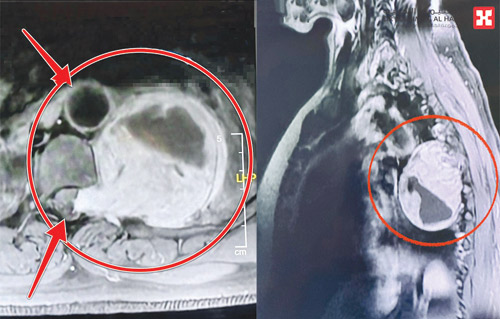

ذكر ذلك د. هاني الجهني استشاري جراحة المخ والأعصاب والعمود الفقري، رئيس الفريق الطبي المعالج. وأضاف أن السيدة راجعت المستشفى وهي تشكو من أعراض متزايدة، مثل صعوبة الحركة على القدمين، والشعور بآلام تبدأ من الظهر وتنتشر إلى أجزاء أخرى من الجسم وصعوبة بالتنفس، وقد أجريت لها عدة فحوصات دقيقة وأظهرت النتائج وجود ورم ضخم ناشئ داخل القناة الشوكية ومتشعب في اتجاه القلب والرئتين، وتسبب في تضيق بالقناة.

واستطر د. الجهني قائلا إنه بعد دراسة الحالة وتحديد الورم والمحيط المتأثر به بدقة، أجريت عملية جراحية للمريضة تم فيها استئصال الورم بدقة وحذر عاليين، مع المحافظة على الحبل الشوكي وغيره من الأعضاء الحساسة، وقد تمت العملية التي استمرت لأربع ساعات متصلة تحت مراقبة الإشارات العصبية في الحبل الشوكي، وكذلك مراقبة أجهزة فحص الاستجابة العصبية، وانتهت بتوفيق من الله بنجاح كامل، وبقيت المريضة في المستشفى 10 أيام بعد العملية حيث تحسنت حالتها الصحية بسرعة كبيرة حيث تمكنت من التحرك على قدميها في اليوم التالي للعملية.